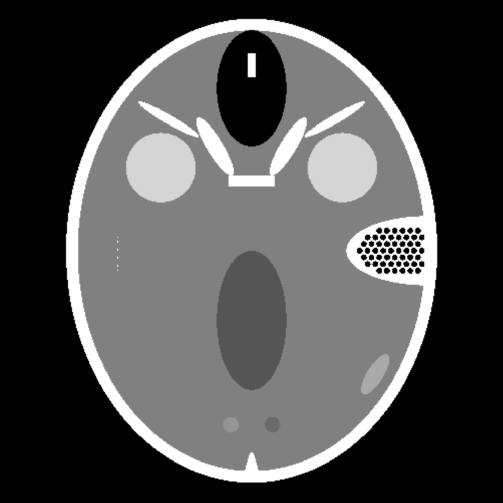

In our experiments, we performed two sets of reconstructions. In our first experiment, we computed reconstructions from synthetic data. Here, we generated limited view spherical mean data in Matlab from a characteristic function of a circle centered around the origin and from the Forbild head phantom [22]. The corresponding Lambda type reconstructions and are shown in Figures 1 and 4. The standard reconstructions without artifact reduction (left images) clearly show the circular artifacts as characterized in Section 4.1, see also Figure 2. In particular, in the reconstruction of Figure 4, we observe that many artifacts overlap and significantly degrade the reconstruction quality (even generating new image features). This is due to the presence of many singularities in the original image. Thus, similar behavior can be expected for any limited view reconstruction of an image with many singularities. By using artifact reduced reconstruction operators , in Figures 1 and 4, we can clearly observe an improvement of image quality. The artifacts are clearly reduced while most of the visible singularities are preserved (even this could not be proven in Section 4.1, see Remark A.1). However, we also observe that some of the visible singularities with directions at the boundary of the limited view are smoothed.

In our second experiment, we computed reconstructions from real photoacoustic measurements. More precisely, we computed the backprojection of the experimental pressure data that were generated through a focused illumination of the object in the plane , and measured by acoustic detectors that were distributed on a circular arc surrounding the object. The data is by courtesy of the group of Prof. Daniel Razansky (Institute for Biological and Medical Imaging, Helmholtz Zentrum München). For more details on the measurement setup we refer to [35]. Although real PAT data is three dimensional in nature, the pressure data (measured in the plane ) of the described sectional imaging setup is related to the circular mean operator by , where denote the circular means of the imaged section, for more details see [6]. Thus, our reconstructions correspond to the application of the operators and to the limited view circular mean data .

The images of Figure 5 show reconstructions of a paper phantom (which has ink as an optical absorber) and images in Figure 6 show reconstructions of a mouse tumor. In Figure 5, one can clearly observe the effect of artifact reduction induced by smooth truncation of the limited view data at the ends of the angular range. As previously, the visible singularities are well preserved while the circular artifacts are removed as can be seen from the difference image in Figure 5. We would like to point our that even though the ground truth is not available the theoretical analysis of Section 4 together with previous examples enable us to differentiate between reliable image features and added artifacts (which are located on circular arcs). This is very important since there are practical situations where it is not that easy to distinguish between reliable image features and artifacts. For example, Figure 6 shows another limited view reconstruction from experimental photoacoustic data where the artifacts are not as distinctive as in Figure 5. The reconstruction with artifact reduction is presented in the middle image of Figure 6. Here, one can observe that a superior image quality is achieved through the application of artifact reduction: the reconstructions appear to be more clear, having a more homogeneous background. As seen from the difference image in Figure 6 the circular artifacts are removed effectively.